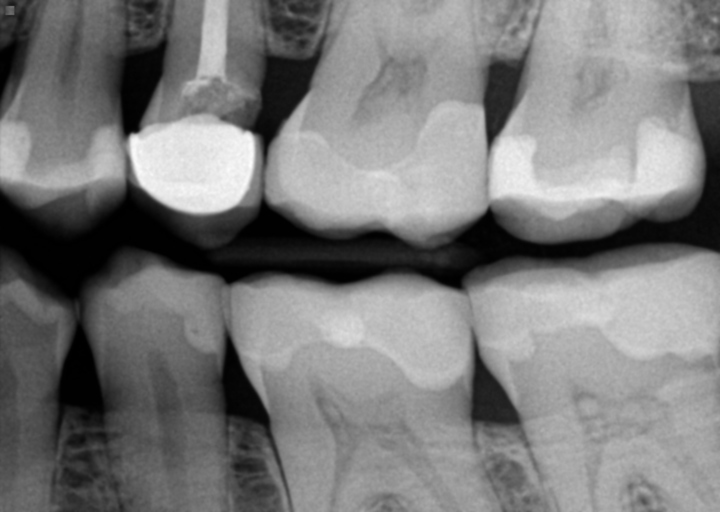

Went to dentist today about loose all porcelain crown over a root canaled tooth. Xray showed no decay, bone loss or fractures. If there's no decay, why is there a only recent, bad bacterial odor at the gum/crown margin? My oral hygeine is excellent, gums are healthy, no bleeding. Dentist not worried. Wants to recement it on in a few days after it loosens more on it's own. Can there be odor but no decay?